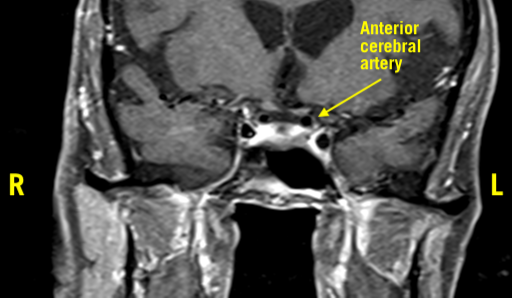

MRI of the orbit was significant for a flattening of the left optic nerve anterior to the optic chiasm, with a prominent flow void from the left anterior cerebral artery (ACA) crossing over the superior aspect of the nerve. Additionally, a mild mass effect was seen inferiorly from the internal carotid artery (ICA), contributing to the compression of the left optic nerve (Figures 1-3).

Figure 3. Prominent flow void from the left ACA crossing over the superior aspect of the optic nerve.